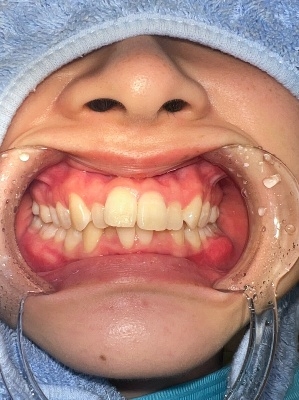

術前口腔内写真 正面観

○前歯の前突した歯を治したい

○八の字型の歯並びを改善したい

○笑った時の歯のアーチを綺麗にしたい